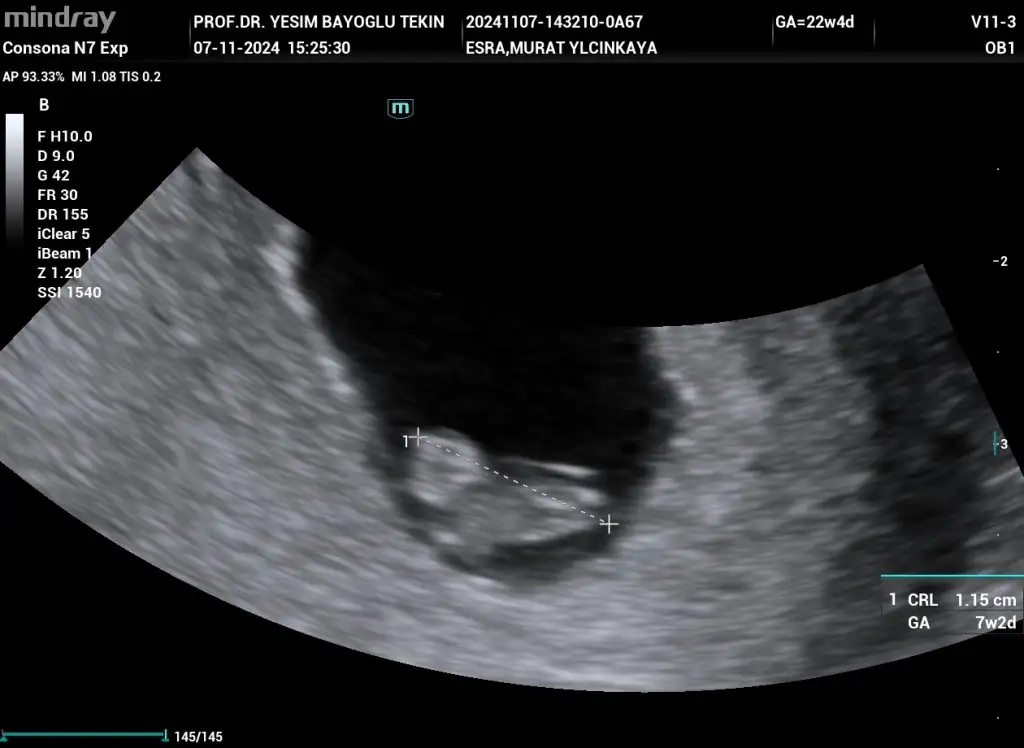

Merhaba benim için de cinsiyet tahmini yapabilir misinizBebek gelişirken cinsel organında bir açı oluşur orada da bir açı var açı dikeyse erkek yatay ise kızdır oradaki açı biraz yatay sizin nub teorisi. Benim kızımda da tutmuştu bu teori

Bana da tahmin de bulunurmusunuzKız cnm

Bana da tahmin de bulunurmusunuzo zaman Allahım gönlünüze göre versin ama inşallah sağlıklı sıhhatli bir kızçe geliyordur

Bana da tahmin de bulunurmusunuzErkek bence cnm

Kaç haftalık bebek canımBana da tahmin de bulunurmusunuz

Merhaba bence kızBana da tahmin de bulunurmusunuz